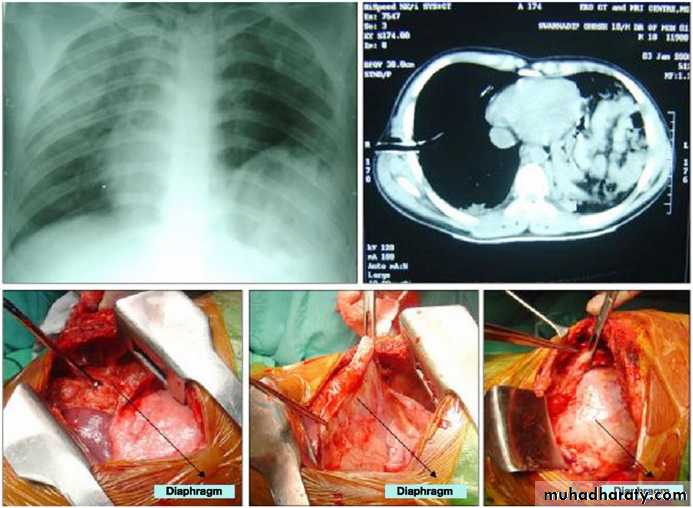

Diaphragmatic rupture

Liver herniation in right side